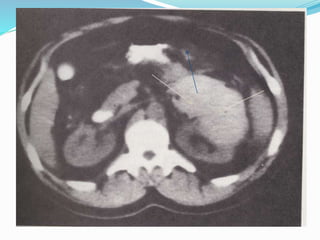

6) Imaging: computed tomography (CT) scan, with and without

intravenous contrast material, in haemodynamically stable

patients.

1) Haemodynamic stabilityshould be assessed upon admission. 2) History: time and setting of incident, past renal surgery, known renal abnormalities. 3) Lab: visible haematuria, dipstick urine analysis, serial haematocrit, baseline serum creatinine. 4) In blunt trauma with visible- or non-visible haematuria and hypotension, a history of rapid deceleration injury and/or significant associated injuries should undergo radiographic evaluation. 5) Any degree of haematuria after penetrating abdominal or thoracic injury requires urgent imaging. 6) Imaging: computed tomography (CT) scan, with and without intravenous contrast material, in haemodynamically stable patients.